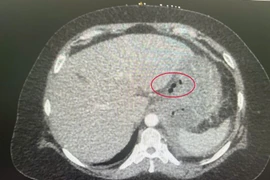

Xương cá đâm thủng, tạo mủ cả tháng trong dạ dày bệnh nhân 56 tuổi

Khi ăn cá, gà, vịt… có nhiều xương cần gỡ xương thật cẩn thận. Khi bị hóc xương nên đến ngay các cơ sở y tế, bệnh viện để được xử lý sớm.